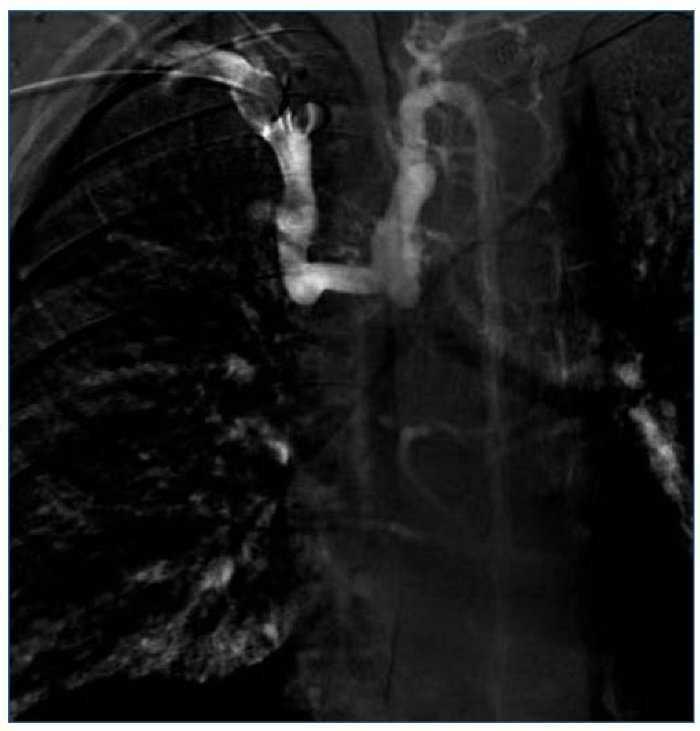

Dos meses más tarde, una nueva EDA observa cordones varicosos en tercio medio, estables. En ese tiempo se realiza flebografía, observando oclusión de la VCS con colateralidad a través del sistema ácigos (figura 1).

Figura 1. Cavografía con oclusión de la vena cava superior y colateralidad a través fundamentalmente del sistema ácigos.